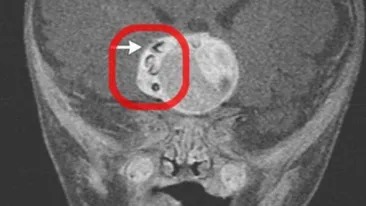

ATENTIE: Imagini socante! Doctorii au facut o descoperire BIZARA in creierul unui bebelus! Nu s-a mai auzit de una ca asta